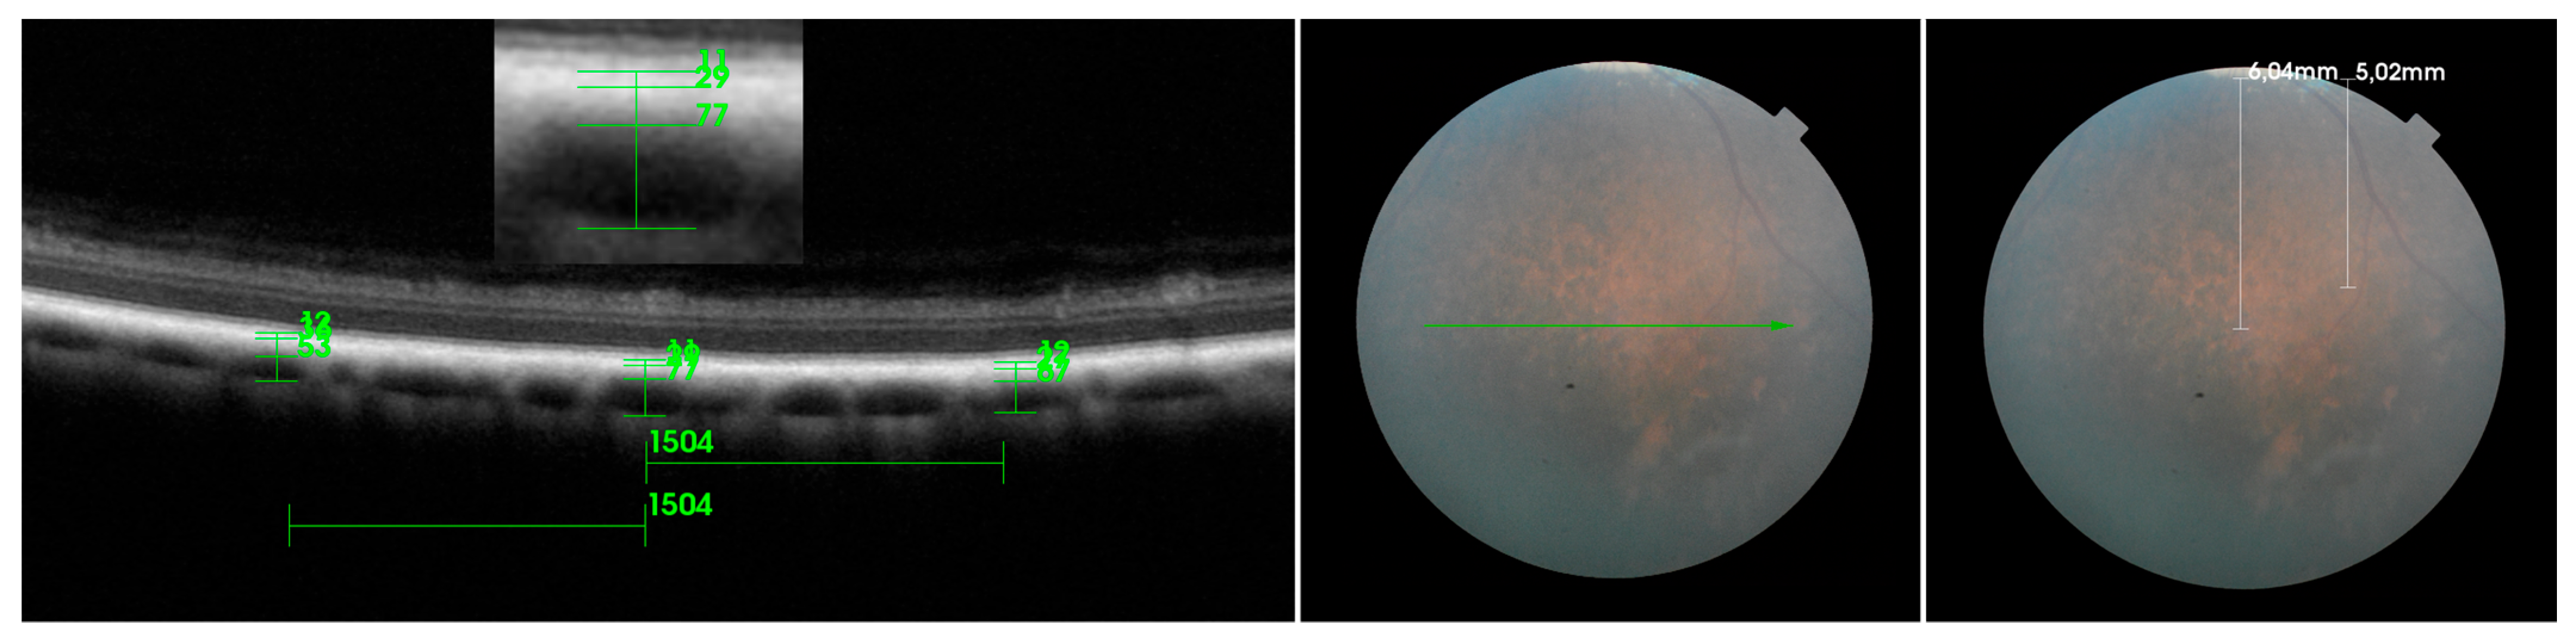

| RPE-BmCc | MSVL | LVLS | WCT | |

|---|---|---|---|---|

| D | ||||

| MA | 28.7 ± 7.49 | 32.59 ± 7.83 | 121.72 ± 24.58 | 183.02 ± 30.15 |

| SN | 26.44 ± 5.04 | 31.62 ± 7.62 | 124.87 ± 28.32 | 182.93 ± 32.01 |

| V | ||||

| MA | 7.71 ± 0.96 | 24.43 ± 8.07 | 78.21 ± 19.22 | 110.24 ± 23.50 |

| SN | 8.13 ± 0.50 | 24.33 ± 6.21 | 75.39 ± 14.28 | 107.84 ± 17.68 |

| TempT | ||||

| MA | 10.76 ± 2.17 | 38.15 ± 7.64 | 126.78 ± 35.78 | 175.69 ± 38.58 |

| SN | 10.90 ± 2.38 | 45.43 ± 10.29 | 125.67 ± 19.96 | 182.00 ± 23.54 |

| TempNT | ||||

| MA | 8.12 ± 0.91 | 27.11 ± 9.87 | 84.45 ± 17.24 | 119.68 ± 24.81 |

| SN | 8.25 ± 0.68 | 30.86 ± 6.94 | 99.59 ± 22.98 | 138.62 ± 26.81 |

| NasT | ||||

| MA | 9.83 ± 1.43 | 32.90 ± 10.02 | 96.78 ± 12.56 | 139.52 ± 15.67 |

| SN | 9.33 ± 1.47 | 33.03 ± 5.40 | 102.33 ± 24.48 | 144.69 ± 24.06 |

| NasNT | ||||

| MA | 8.05 ± 0.86 | 26.34 ± 8.90 | 89.72 ± 14.19 | 124.12 ± 19.40 |

| SN | 8.44 ± 0.69 | 29.74 ± 7.50 | 90.59 ± 12.43 | 128.77 ± 16.89 |